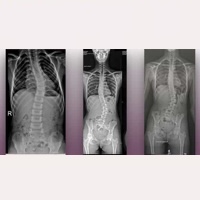

当研究所はスペイン・バルセロナにある最先端の医療センターとして、16言語で患者さんのサポートを行っております。アーノルド・キアリI型症候群、特発性脊髄空洞症、特発性脊柱側弯症などに対し、従来の治療法とは異なる、身体への負担が少なく特記すべき合併症のない、早期回復が期待できる原因除去手術を提供しており、これまでに良好な治療成績を収めています。

治療対象となる病気